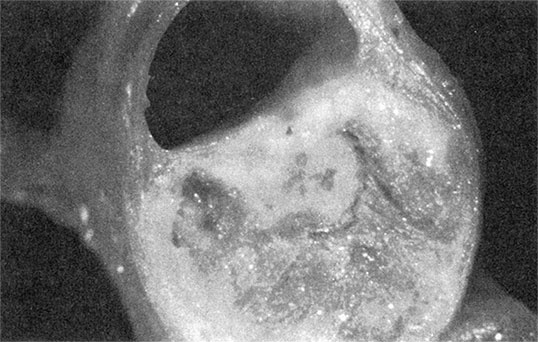

Разрастание атеросклеротических бляшек – тревожный симптом. По мере увеличения они имеют свойство разрываться (см. рис. 1.7а). Ранее ученые считали, что с большей вероятностью отрываются те бляшки, которые сильнее выдаются в просвет сосуда, т. е. вызывают более высокую степень стеноза (сужения) сосуда. Сейчас известно, что наиболее частой причиной коронарных событий являются нестабильные бляшки: они сужают просвет сосуда всего на 30–50 %, но при этом их липидное ядро окружено лишь тонким слоем соединительной ткани (см. рис. 1.7б). У многих людей с атеросклерозом имеется несколько бляшек с меньшей степенью стеноза. Бляшки, сужающие просвет сосуда на 70–90 %, встречаются относительно редко, но всегда угрожают повышенным риском неблагоприятных последствий (см. рис. 1.7в).

Рисунок 1.7б. Нестабильная бляшка, отделенная от внутреннего просвета сосуда лишь тонким слоем клеток, имеет большую вероятность разрыва. Снимок предоставлен доктором Майклом Дж. Дэвисом